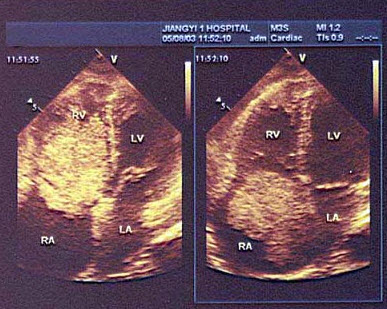

136、单项选择题

根据心尖四腔切面声像图所示,超声诊断为()

A.右房血栓

B.三尖瓣赘生物

C.右房黏液瘤

D.正常声像图

E.二尖瓣脱垂